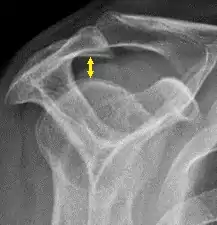

Supraspinatus outlet view X-ray, showing subacromial space measurement

• The normal subacromial space in shoulder radiographs is 9–10 mm; this space is significantly greater in men, with a slight reduction with age.[2] In middle age, a subacromial space less than 6 mm is pathological, and may indicate a rupture of the tendon of the supraspinatus muscle.[2]